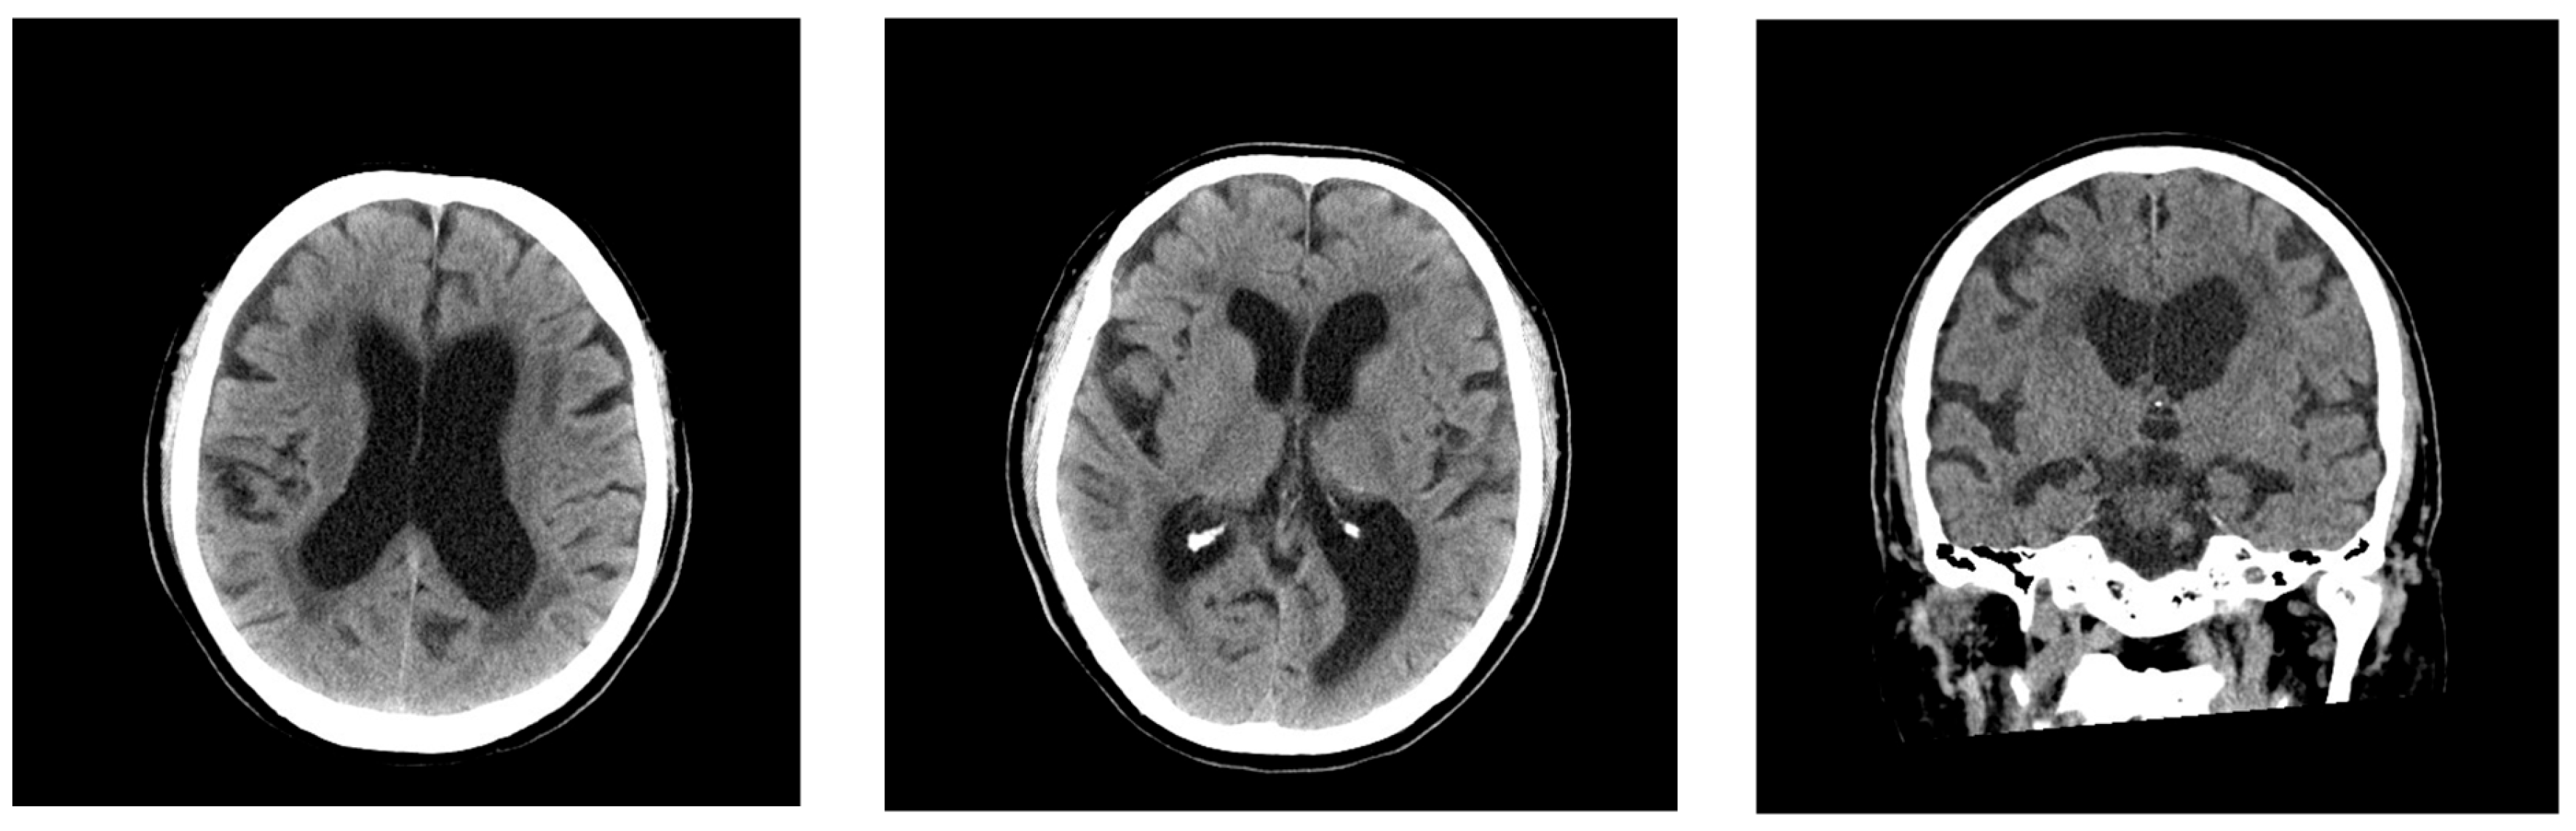

2.1. Case 1